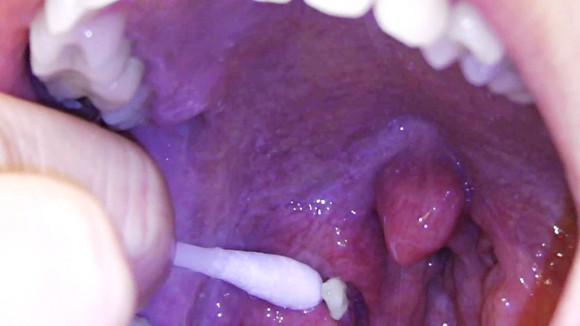

편도 결석이 작으면 집에서 뽑을 수 있어요. 칫솔 뒷면이나 면봉으로 부드럽게 긁는 것입니다. 워터픽이나 가글 등으로도 뺄 수 있습니다. 단, 편도 결석을 제거하는 방법을 너무 쉽게 생각해서 무리한 힘을 가하면 입안이 찢어지고 다른 감염에 의한 염증이 발생합니다.편도 결석으로 병원에 가야 할 때